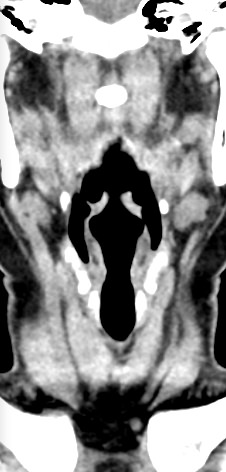

Оптимальным методом обследования гортани и голосовых связок является мультиспиральная компьютерная томография. Метод позволяет подробно визуализировать состояние данной анатомической области и выявить патологические изменения, которые незаметны при ларингоскопии (визуальный осмотр гортани с помощью специальных инструментов), проведении УЗИ и обычной рентгенографии.

Компьютерная томография особенно полезна для оценки состояния хрящей гортани, которые лучше всего визуализируются с помощью данного исследования. В частности, мультиспиральная КТ позволяет выявить распространение рака гортани в ткань щитовидного хряща и другие окружающие структуры.

На полученных снимках можно оценить состояние всех структурных элементов гортани, голосовых складок, хрящей, а также лимфатических узлов, сосудов и шейных позвонков на исследуемом уровне. Инновационные возможности аппарата позволяют построить 3D-модель зоны исследования, которая дает наглядную картину пространственного расположения органов, что бывает особенно важно при планировании хирургических операций.